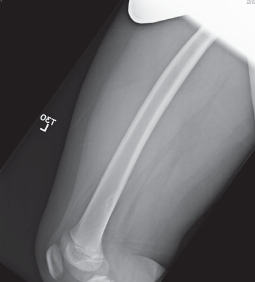

Danielle Massarella, MD; David Effron, MD

A 9-year-old African American female presented with a painless left thigh swelling first noted 3 weeks prior, which had been slightly increasing in size over.